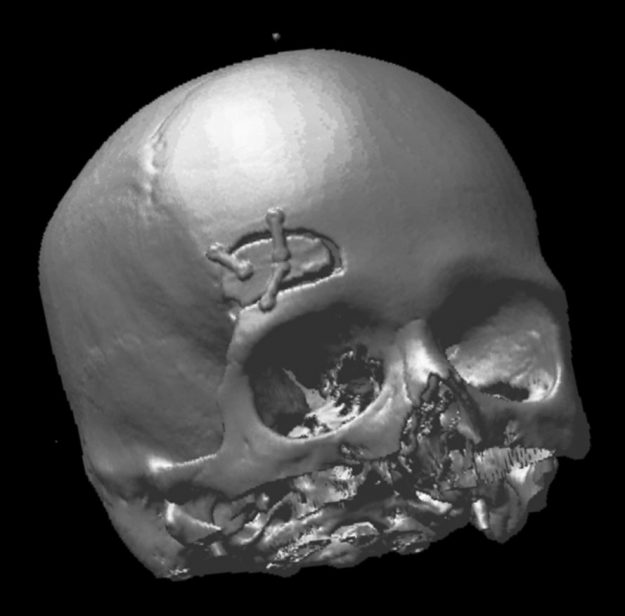

Ασθενής γυναίκα 58 ετών με πονοκεφάλους και διαταραχές όρασης. Ο οφθαλμολογικός έλεγχος έδειξε οίδημα οπτικών θηλών άμφω και σημαντικό περιορισμό των οπτικών πεδίων. Τα συμπτώματα της ασθενούς ήταν προοδευτικά επιδεινούμενα, το ίδιο και οι εξετάσεις της. Η μαγνητική εγκεφάλου ανέδειξε ευμεγέθη αραχνοειδή κύστη δεξιά κροταφικά με σημαντική πίεση επί του υγιούς εγκεφάλου και παρεκτόπιση των…